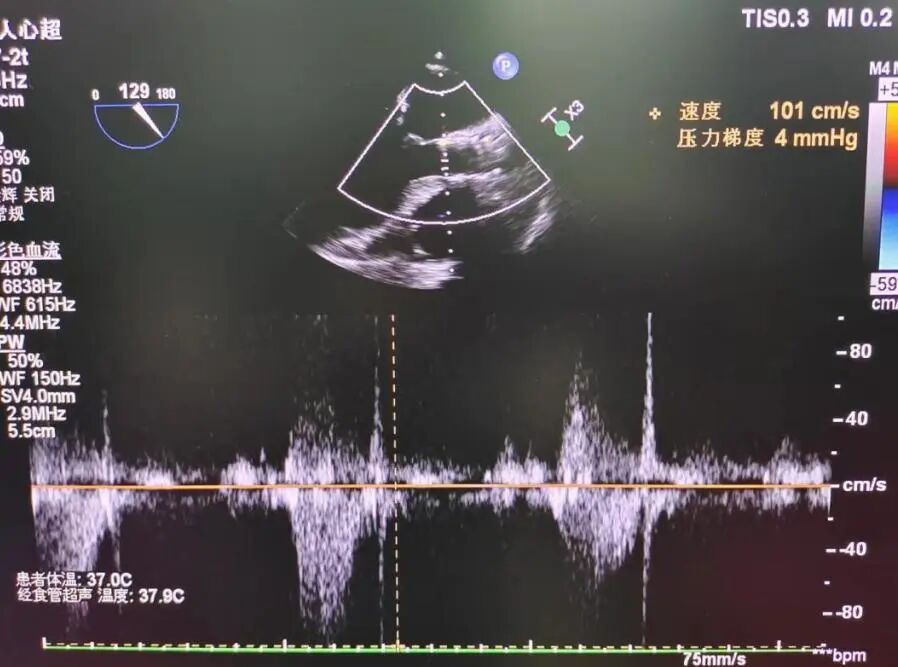

超声看位置合适,无反流

患者压差从64mmHg降为4mmHg,效果显著。